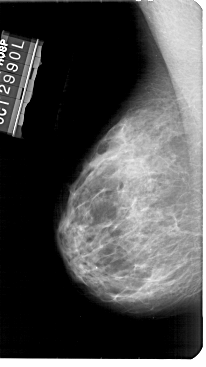

A_1949_1.LEFT_MLO

LEFT_MLO LINES 5491 PIXELS_PER_LINE 3076 BITS_PER_PIXEL 12 RESOLUTION 43.5 NON_OVERLAY